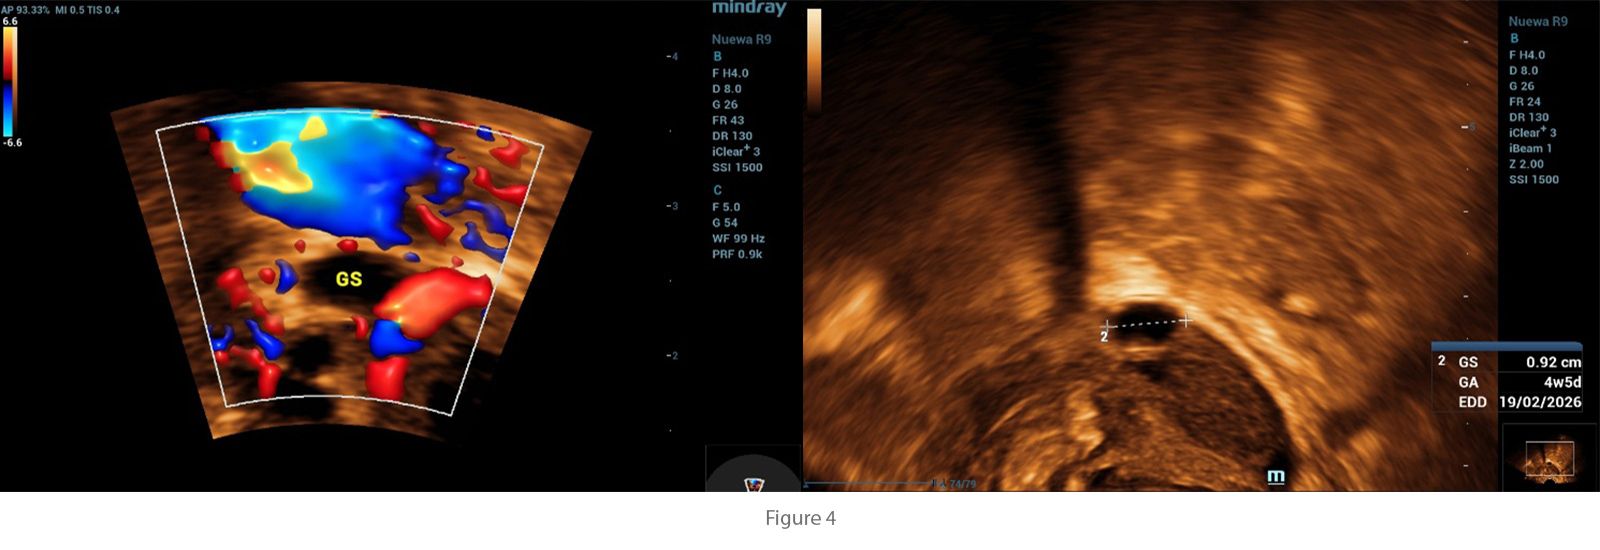

Initial investigations included a urine pregnancy test, which returned positive. Transvaginal ultrasound was performed, revealing an anteverted, non-gravid uterus with no abnormal myometrial shadowing. The endometrium measured 14.2 mm.?

All ultrasound examinations were performed using the Nuewa R9 Ultrasound System (Mindray, Shenzhen, China). A convex transducer (SC6-1U) was employed for general pelvic evaluation, and a 4D transvaginal transducer (DE11-3WU) was used for detailed assessment of the uterus and adnexa. Imaging modalities included two-dimensional (2D) grayscale ultrasound, Color Doppler, and four-dimensional (4D) imaging.

To enhance diagnostic accuracy, advanced imaging applications were applied. Smart Endometrial Receptivity Analysis (Smart ERA) was utilized to assess endometrial morphology and volume, while the SCV+ function was employed to improve spatial resolution and delineation of adnexal structures. These features contributed to the precise characterization of the ectopic gestational sac and detailed evaluation of ovarian and endometrial parameters.

In this case, transvaginal ultrasound was central to the diagnosis. The examination revealed the absence of an intrauterine gestational sac despite a positive pregnancy test, a finding highly suggestive of ectopic pregnancy. Additionally, a small gestational sac was visualized outside the uterine cavity, confirming the diagnosis. These ultrasound findings, when correlated with the patientŌĆÖs symptoms of abdominal pain and vaginal spotting, highlight the critical role of transvaginal imaging in detecting ectopic pregnancies at an early stage, enabling prompt intervention and reducing the risk of complications.